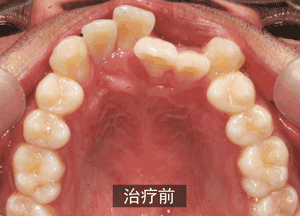

比如,这位患者朋友,在做矫正之前牙齿是这样的:

由于牙齿过于不整齐,患者拔除了四颗牙齿(上牙和下牙各拔两颗),然后通过戴牙套的方式,进行牙齿矫正,牙齿明显变的整齐: